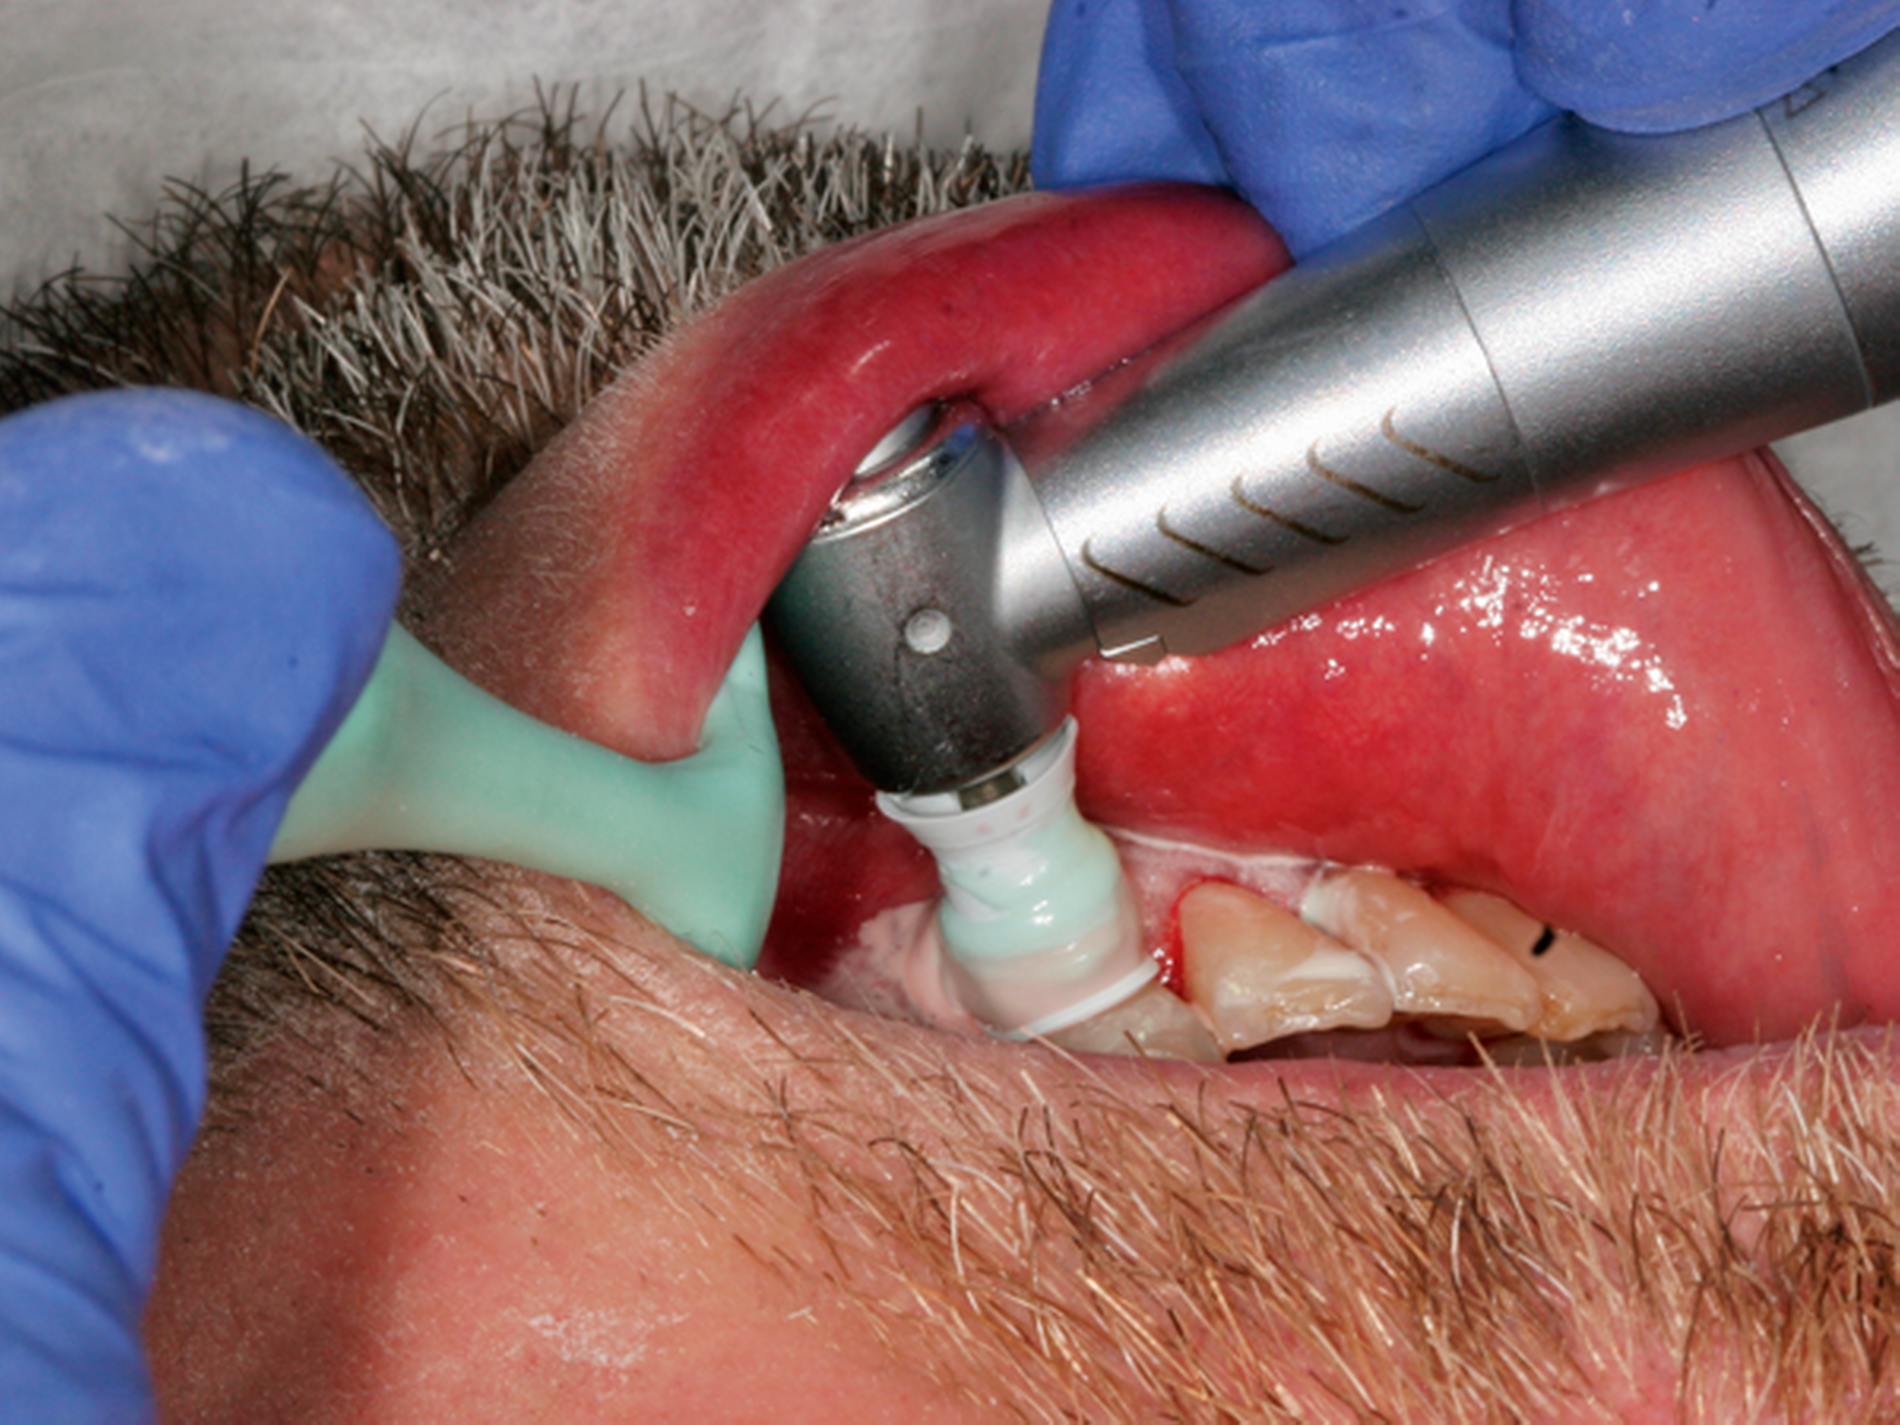

Abb. 1: Interventionen zur Instruktion und Motivation des häuslichen supragingivalen Biofilmmanagments im Rahmen einer UPT-Sitzung: Der 50-jährige Patient befindet sich im dritten Jahr nach der zweiten Therapiestufe und hat ein reduziertes, aber gesundes Parodont.

Häufig können – beispielsweise bei Patienten mit Parodontitis Stadium III oder IV – nicht alle Therapieziele vollständig bei allen Zähnen realisiert werden. Deshalb müssen unter Berücksichtigung der wissenschaftlichen Evidenz individuelle Interventionen in der UPT ergriffen werden, die abhängig vom gingivalen und parodontalen Status sind und dabei die präventiven und therapeutischen Interventionen aus der ersten und der zweiten Therapiestufe kombinieren. Diese professionellen Maßnahmen müssen durch eine Aufrechterhaltung der Motivation zur kontinuierlichen Mitarbeit der Patienten flankiert werden. Das bedingt eine regelmäßige, individuell an die Bedürfnisse des Patienten angepasste Betreuung.